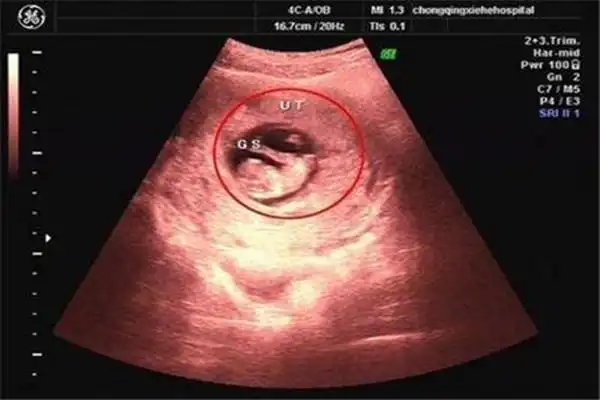

六周的孕囊能看出怀几个孩子吗孕早期通过孕囊形状看男女不靠谱

孕囊形状为圆形就代表一定是生女孩吗

孕囊的形状一般是呈椭圆形或者是月亮型.

3孕囊数据等差递减